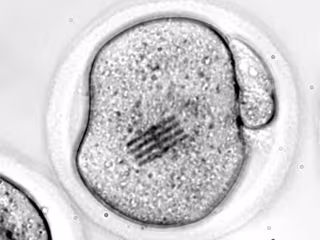

Embrión con un chip en su citoplasma

Embrión con un chip en su citoplasma - REMITIDA UGR

Los científicos han inyectado el chip en el interior de un óvulo de ratón junto con un espermatozoide para estudiar las etapas iniciales de la fertilización, según detalla en una nota la UGR.

Con el chip dentro, los científicos han podido medir las fuerzas que reorganizan el interior del óvulo, es decir, su citoplasma, desde que se introduce el espermatozoide hasta que se divide en dos células.